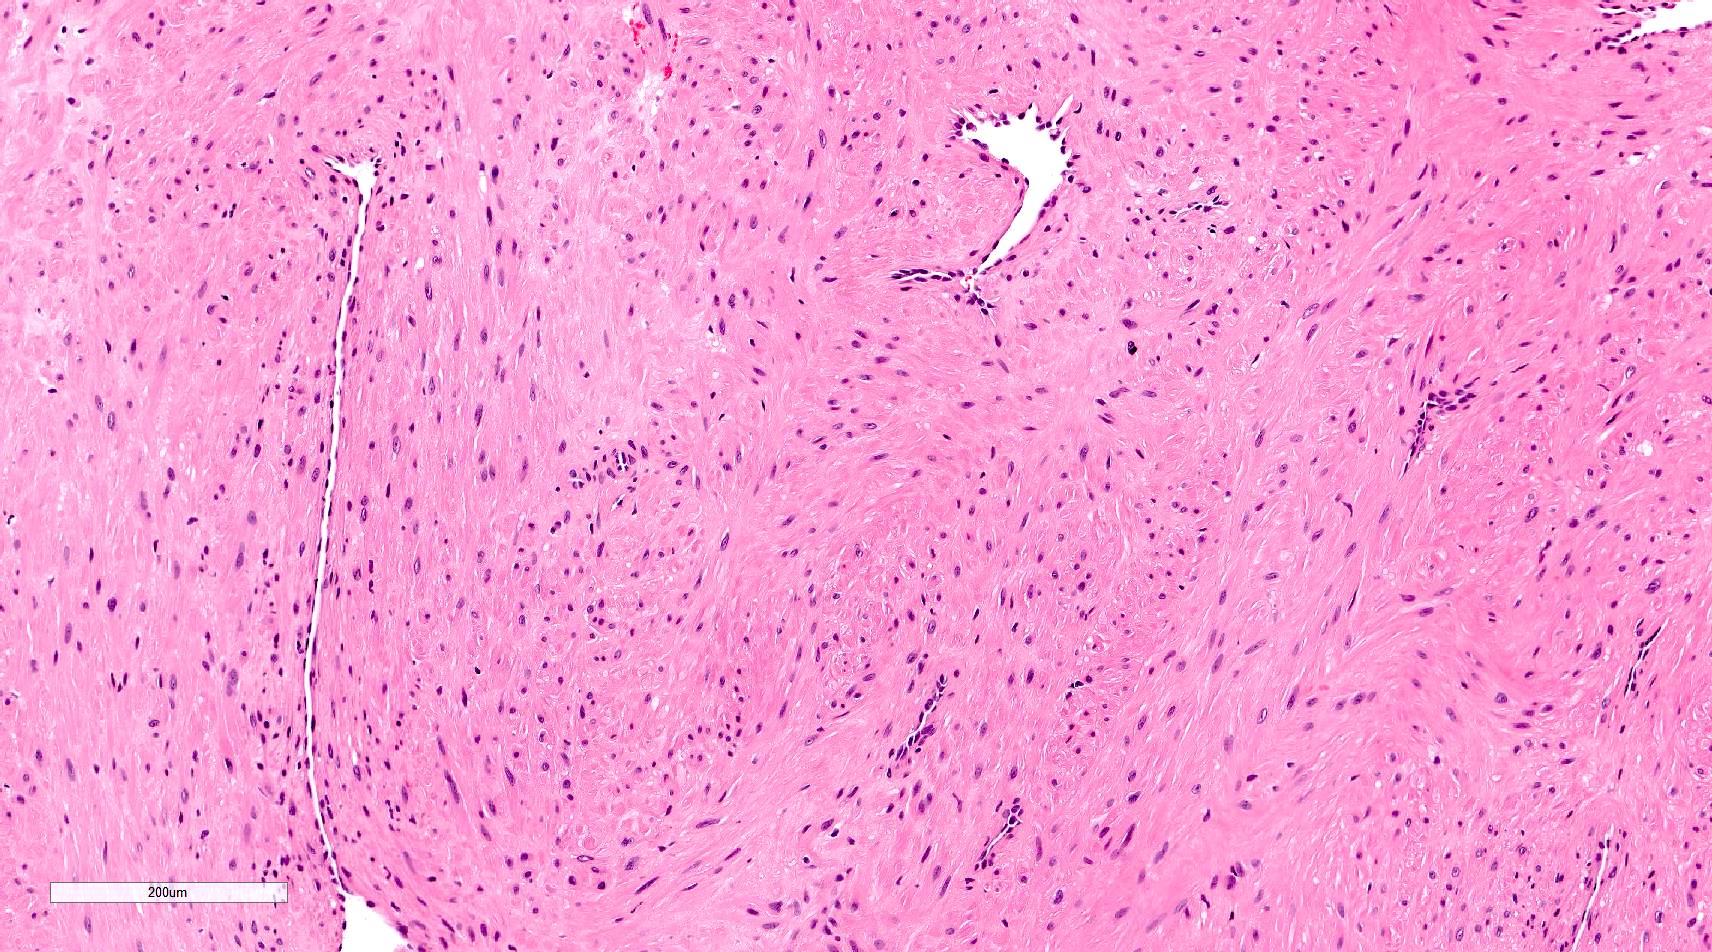

Microscopic (histologic) description

- Encapsulated proliferation of eosinophilic smooth muscle cells with minimal nuclear pleomorphism

- Rounded or slit-like veins with muscular walls present within the tumor (J Cutan Pathol 2017;44:342)

- Tumors can further be classified into 3 subcategories, first described by Morimoto et al:

- Solid type: smooth muscle bundles surround numerous small slit-like channels

- Cavernous type: dilated vascular channels, the walls of which are difficult to distinguish from the intervascular smooth muscle

- Venous type: thick walled vessels that are easily distinguished from the intervascular smooth muscle

Microscopic (histologic) images

Contributed by Ohoud Aljarbou, M.D., Jijgee Munkhdelger, M.D., Ph.D. and Andrey Bychkov, M.D., Ph.D.

A. Angioleiomyoma. A mixture of smooth muscle bundles arranged in small fascicles and intervening vascular channels is noted. The concentric perivascular spindle cell proliferation which is characteristic for myopericytoma is absent. There are no glomus cells seen. Adipocytes are not seen in this image, which makes angiomyolipoma less likely.